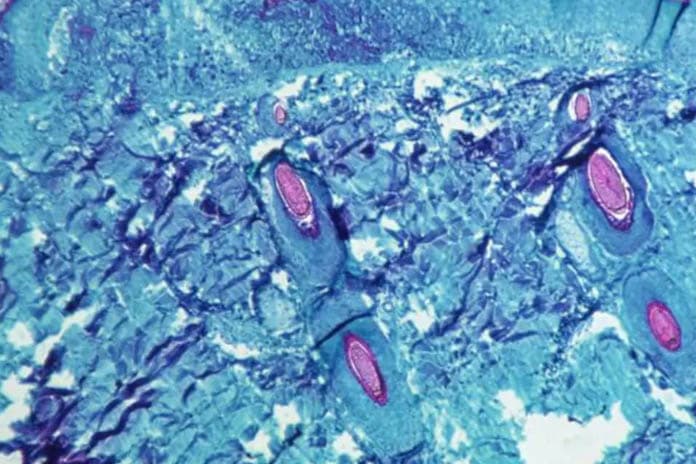

疾病管制署(下稱疾管署)今(2)日公布國內新增12例猴痘(Mpox)本土病例,為11例本國籍及1例外國籍男性,分別位於北部11例及中部1例,年齡介於20多歲至40多歲,發病日介於今(2023)年4月10日至4月23日,因身體陸續出現發燒、淋巴腺腫大、水泡、膿疱等症狀,經醫師評估後採檢通報,分別於4月26日至5月1日確診。經疫調匡列相關高風險接觸者24名,已進行衛教並自我健康監測21天。

疾管署提醒,猴痘傳播對象具侷限性,此波疫情以親密接觸之人際傳播為主,提醒民眾前往流行地區或國內風險場域,應落實自我防護,並避免出入可能與不特定人士親密接觸之社交活動等風險場域,如出現皮膚病灶,例如:皮疹、水泡、斑疹、斑丘疹、膿疱等,以及發燒、畏寒/寒顫、頭痛、肌肉痛、背痛、關節痛、淋巴腺腫大(如耳周、腋窩、頸部或腹股溝等處)等疑似症狀,應佩戴口罩儘速就醫,並主動告知醫師旅遊史、高風險場域暴露史及接觸史。相關資訊可至疾管署全球資訊網(https://www.cdc.gov.tw)或撥打國內免付費防疫專線1922(或0800-001922)洽詢。